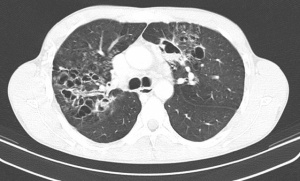

Der Beitrag thematisiert Leben und Wirken von Oberstarzt Prof. Dr. Paul Schürmann, Namensgeber des 1966 gestifteten Preises der VdSO e. V. (heute DGWMP e. V.). Als bedeutender Wissenschaftler und Tuberkuloseforscher in den zwanziger und dreißiger Jahren des 20. Jahrhunderts beendete er seine universitäre Karriere an der Charité aus politischen Gründen und wechselte als Sanitätsoffizier an die wiederbegründete Militärärztliche Akademie. Dort baute er das Institut für Allgemeine und Wehrpathologie auf und avancierte zum Lehrgruppenkommandeur der Forschungsabteilung. Bei der Anfertigung von Dokumentationsfilmen über den Sanitätsdienst fiel er im Juli 1941 in Russland. In der Arbeit soll der aktuelle Forschungsstand zu Paul Schürmann auch vor dem Hintergrund der Medizin im NS-System wiedergegeben und diskutiert werden, in welches Spannungsfeld man auch als Arzt und Sanitätsoffizier mit festem moralischem Kompass in einem durch Ideologie infizierten wissenschaftlichen Umfeld kommen konnte.